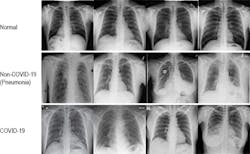

Cognex’s researchers analyzed nearly 14,000 X-ray images in the COVID-Net data set. The images were divided into three categories: normal, non-COVID-19 pneumonia, and COVID-19.

As this table comparing multiple deep learning packages shows, COVID-Net generated strong predictive results, ranging from 92.6% on normal images to 94.7% for COVID-19 images. VisionPro Deep Learning 1.0 did even better, with 95.6% on normal X-rays and 97.0% on COVID-19 X-rays.